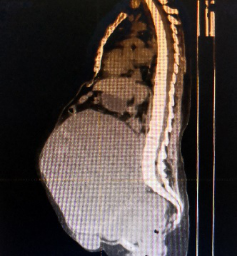

腹部巨大包块影像检查

入院后,团队对王女士进行了详细的身体检查,一方面排除血栓的可能,并予以低分子肝素对症治疗,另一方面考虑到患者左侧胸腔积水,请胸外科进行胸腔穿刺引流,并由介入科对盆腔的巨大包块进行造影检查,明确了包块血供不是来源于大血管,麻醉科、输血科、SICU等科室进行了多学科会诊,充分做好了手术准备。

3月25日,在充分告知相关手术风险后,上海十院妇产科程忠平团队为王女士进行了“盆腔肿瘤切除术+肠粘连松解术+大网膜切除术+子宫颈切除术+双侧卵巢切除术+盆腔淋巴结切除术+腹壁肿瘤切除术”。术中发现盆腔包块来源于左侧卵巢,其血供主要来源于横结肠及肠系膜,包块与肠管和系膜无明显界限,因此在术中又邀请了普外科周波主任共同手术,分开了肿块,保住了肠管。

术中发现患者盆腔包块里的囊液足足有6000ml,实体包块净重3.5kg,病理结果确认是子宫平滑肌肉瘤。经历长达6小时后,手术取得成功,患者安返ICU,在ICU观察一夜后,第二天就转回妇科病房。虽说手术对王女士来说这次手术只是第一步,后续还需要化疗,但是终于可以不再携带着近20斤的包块生活了,八年来重新赢回自由呼吸、自如活动,让她和家人都感激不已。10天后患者康复出院,出院时特意送来了3面锦旗表达感谢。